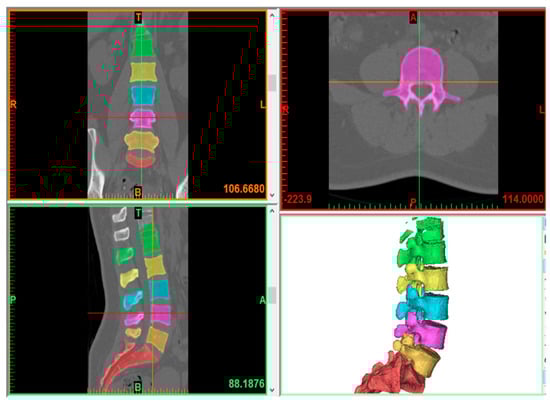

2.1. Model Creation